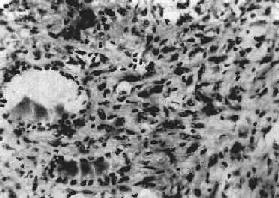

3.未分化(undifferentiated carcinoma)约占甲状腺15%,恶性度高,生长快,早期即可向周围组织浸润并发生转移。患者多在50岁以上,无男女差别。肉眼观,切面灰白色,常有出血、坏死。根据组织形态可分为小细胞型、巨细胞型和梭形细胞型。小细胞型由小圆形细胞构成,呈弥漫分布,与恶性淋巴颇相似,用免疫组化鉴别,如细胞显示角蛋白(Keratin)或胚抗原(CEA),则可确定其来源于上皮组织。巨细胞型预后最差,镜下细胞大小不一,形态各异,常有巨核细胞及多核巨细胞(图15-12)。

图15-12 甲状腺未分化

细胞异型性明显,可见巨核细胞